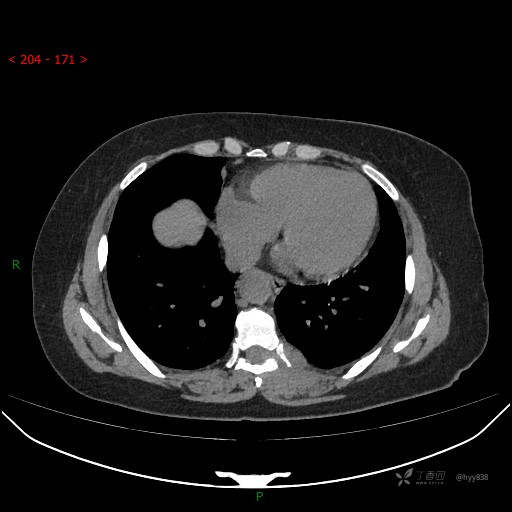

增强